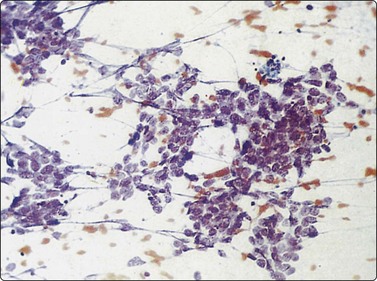

image image image

Fig. 8.28 High-grade neuroendocrine carcinoma; small cell carcinoma

(A, B) Smears showing ‘intermediate’ morphology. Loose aggregates of fragile cells with traumatization artifact and nuclear molding but some background cytoplasm (A, Pap, MP; B, H&E, HP). (C) Tissue section of resected peripheral stage 1 small cell carcinoma (H&E, HP).

image image image image image

Fig. 8.29 High-grade neuroendocrine carcinoma

Variable morphology including small cell and large cell patterns. (A) Low-power smear appearances of small cell carcinoma; (B) Higher-power examination shows some large cells with prominent nucleoli (A, H&E, LP; B, H&E, MP). (C,D) Tissue sections of resected peripheral stage 1 tumor showing areas of geographic necrosis and a predominance of large cells with prominent nucleoli (C, tissue section, H&E, LP, Inset, HP; D, tissue section, H&E, HP). (E) Positive immunostaining for chromogranin in resected specimen (E, tissue section, IPOX, HP).